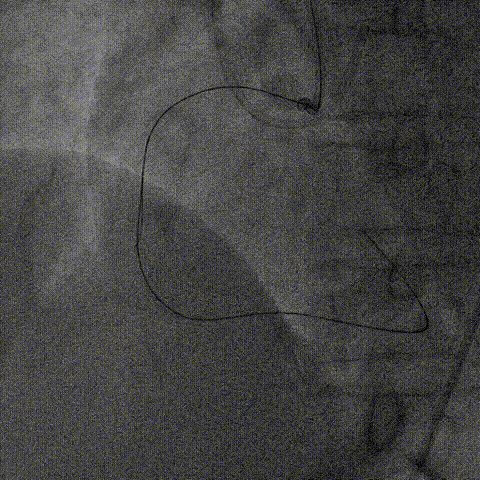

器械通过困难:

1、2.0mm顺应性球囊预扩后,Telescope™支撑下火山血管内超声(头端直径较大)无法通过,操作过程中右冠系统脱出,重新放置右冠指引管后在逆向导丝指引下正向导丝再次通过病变至右冠远端。

2、换用2.75非顺应性球囊在Telescope™支撑下扩张闭塞段并引导Telescope™通过闭塞段后完成血管内超声检查。

内腔同时兼容2.0mm球囊及Finecross微导管